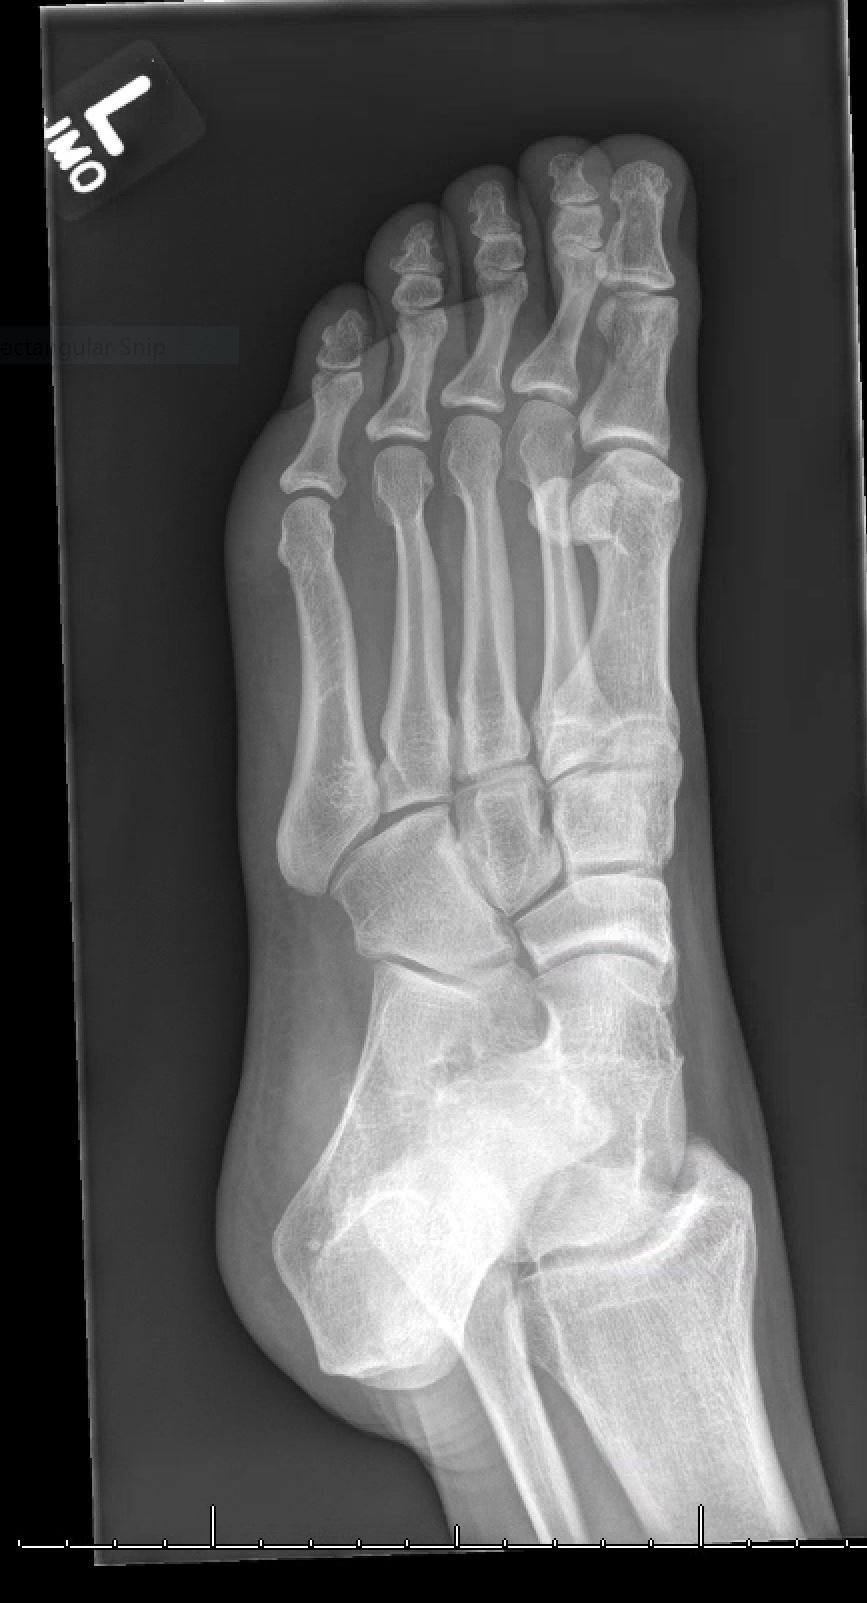

X-rays of the foot were obtained and no radiopaque foreign body was visualized. Due to high clinical suspicion for retained foreign body, a point-of-care ultrasound was performed by applying a high-frequency linear probe at the area of discomfort. In the long axis an ovoid focus of hypoechogenicity (orange outline) is visualized. Within this finding there is a linear focus (yellow line) of increased echogenicity measuring 1 mm in diameter and 1 cm in length. On short axis view, a rectangle focus (green dot) demonstrating shadowing (blue highlight) is seen.

Whenever a patient has a traumatic injury that violates the integrity of the body, there is the possibility of a retained foreign body. It has been reported that missed foreign bodies are the second leading cause of lawsuits in emergency medicine.1 Despite the known risk of litigation, greater than one third of foreign bodies are missed initially on examination.2 This has frequently been attributed to a lack of imaging in conjunction with examination.3 X-rays are thought to be the most common imaging to screen for foreign bodies in extremity trauma.4 Unfortunately, many foreign bodies are not radiopaque on X-ray. Radiopaque foreign bodies are usually more dense than soft tissues and similar to bone density (e.g., metal, stone, or certain types of glass).5 Less dense foreign bodies are radiolucent and not seen on X-ray.